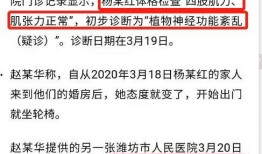

杨晓红家暴最新爆料,最新爆料揭露惊人内幕

最近网上可是炸开了锅,杨晓红家暴的最新爆料简直让人瞠目结舌!你有没有听说?今天,我就来给你细细道来,让你一探究竟。一、事件回顾:...

2025-08-29 49 -